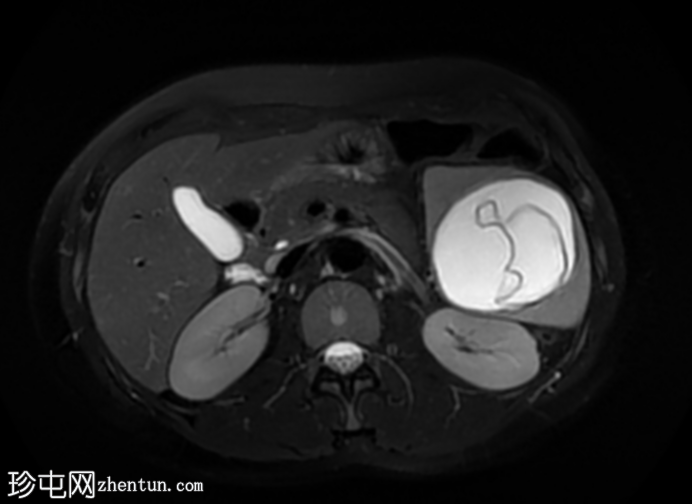

轴位

STIR序列

肝脏肿大,可见多发性双叶肝囊肿。

脾脏肿大,可见多发性大囊肿,内层脱离。

肝脾包虫囊肿的典型

影像

学表现。